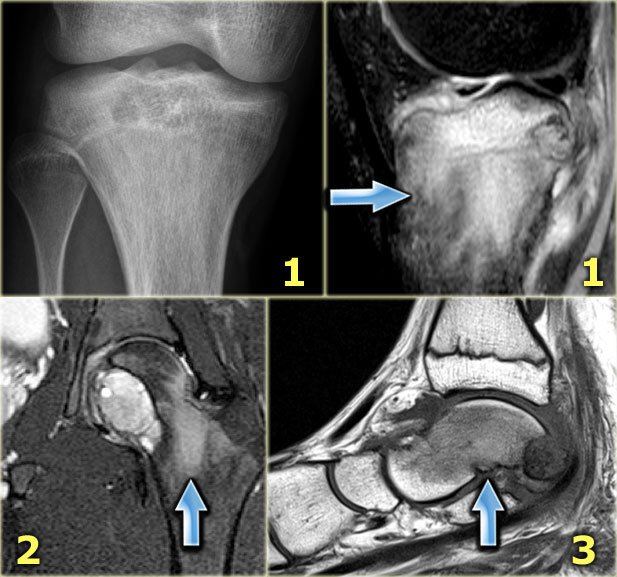

Chondroblastoma (6)

Edema is almost always present in chondroblastoma.

Here some examples:

1. Typical chondroblastoma with epiphyseal localization. Some reactive sclerosis and abundant perilesional edema on T2-weighted image with fat saturation.

2. Coronal T2-weighted image with fat saturation demonstratesa chondroblastoma in the femur epiphysis with perilesional edema (same case as above).

3. Sagittal T1-weighted MR image of a lytic lesion with peripheral sclerotic rim in the posterior talar bone in a young patient.

The lesion is hypointense, well-defined with a low intensity rim.

The bone marrow has a low signal intensity due to extensive edema (arrow).